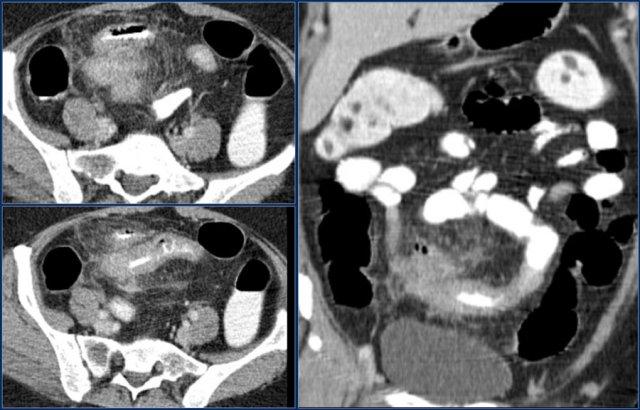

Mũi tên đỏ chỉ vào đại tràng sigma, đang chứa đầy phân. Do đó đây không phải là dấu hiệu phân trong ruột non.

Các dấu hiệu hình ảnh:

- Tổn thương gây tắc nghẽn ở hồi tràng với bờ dạng vai dẫn đến tắc ruột non (mũi tên vàng).

Có thể cân nhắc chẩn đoán bệnh Crohn.

Tuy nhiên bệnh nhân này không có tiền sử bệnh Crohn và hồi tràng tận (không hiển thị) bình thường, điều này sẽ không điển hình cho bệnh Crohn.

Kết quả phẫu thuật xác nhận đây là ung thư biểu mô tuyến.

Đây là một trường hợp ung thư biểu mô tuyến khác ở hỗng tràng.

Có nhiều hạch bạch huyết (mũi tên đỏ) và thâm nhiễm mỡ (mũi tên vàng).

Không nên nhầm lẫn với viêm mỡ mạc treo vì các hạch bạch huyết hoại tử lớn này là bệnh lý.